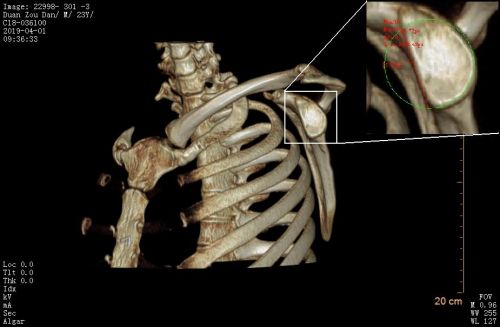

患者影像。

由于左肩脱位症状极重,患者入院当天早上再次发生脱位。CT检查发现,左肩胛盂有较大的骨缺损,缺损面积大约为15X35mm,相当于正常肩胛盂面积的30%。目前,针对此类肩胛盂(骨缺损>20%)修复,指南建议使用临近的喙突移植肩胛骨以修补骨性缺损(Lartarjet术),但不幸的是患者喙突发育不良,小于骨缺损体积,Lartarjet术没有条件实施。王靖果断决定利用髂骨来修复肩胛盂。该手术在关节镜下实施难度极大,是省内首次报道,同时也为肩关节脱位合并巨大肩胛盂缺损患者提供了肩关节镜微创治疗的新方法。术后复查CT可见左肩胛盂前方有一块移植髂骨块挡住了肱骨头脱位的轨迹。